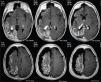

En algunas oportunidades es muy difícil de diagnosticar, ya que pueden ser alteraciones microscópicas invisibles a la RM, aunque esta sea de alta resolución, como ocurre especialmente en los casos de DC tipo I. A lo anterior debemos agregar que en niños menores de dos años sus cerebros están madurando y van variando la cantidad de agua y progresivamente va produciéndose la mielinización. Entonces las imágenes de RM pueden ser muy variables en los primeros 24 meses, pasando a estabilizarse luego de dos años; por lo tanto una RM normal antes de los dos años no garantiza que lo será a futuro. La sensibilidad para detectar DC de una RM realizada con protocolo de epilepsia no supera el 66%. El PET (Positron emission tomography) con un 80% es el examen de mayor sensibilidad en el estudio de las DC (29). Por lo tanto el abordaje diagnóstico de las DC debe ser multimodal (EEG, RM, PET, etc.). En nuestra institución tenemos excelentes resultados en evaluar la zona epileptógena con PET, tanto inter-ictal, como ictal, aunque la RM sea normal o no concluyente (Figura 3). El control de crisis llega hasta un 80% cuando la resección de la DC es completa, pero cae a solo un 20%, cuando la resección es incompleta (29).

Niño portador de epilepsia refractaria evaluado por primera vez en el año 2004 en otra institución. Presenta crisis focales caracterizadas por extensión de extremidad superior izquierda. En el video EEG las crisis se inician en la región posterior derecha (parietal), además de abundante actividad inter-ictal de la misma localización. Dado que su RM es normal se descartó cirugía. Pero vuelve a consultar en nuestra institución seis años después y se realiza PET, el que muestra hipometabolismo parietal derecho y nueva RM volumétrica de alta resolución ponderada en T1, revela lesión compatible con displasia cortical en la misma zona del hipometabolismo (Fig. 3, flechas), el caso fue estudiado con ECoG crónica y la patología correspondió a una DC IIB. El paciente permanece libre de crisis con seguimiento de tres años. Este caso enfatiza la necesidad de repetir RM con imágenes avanzadas, cuando se tiene una primera RM normal y un PET anormal.